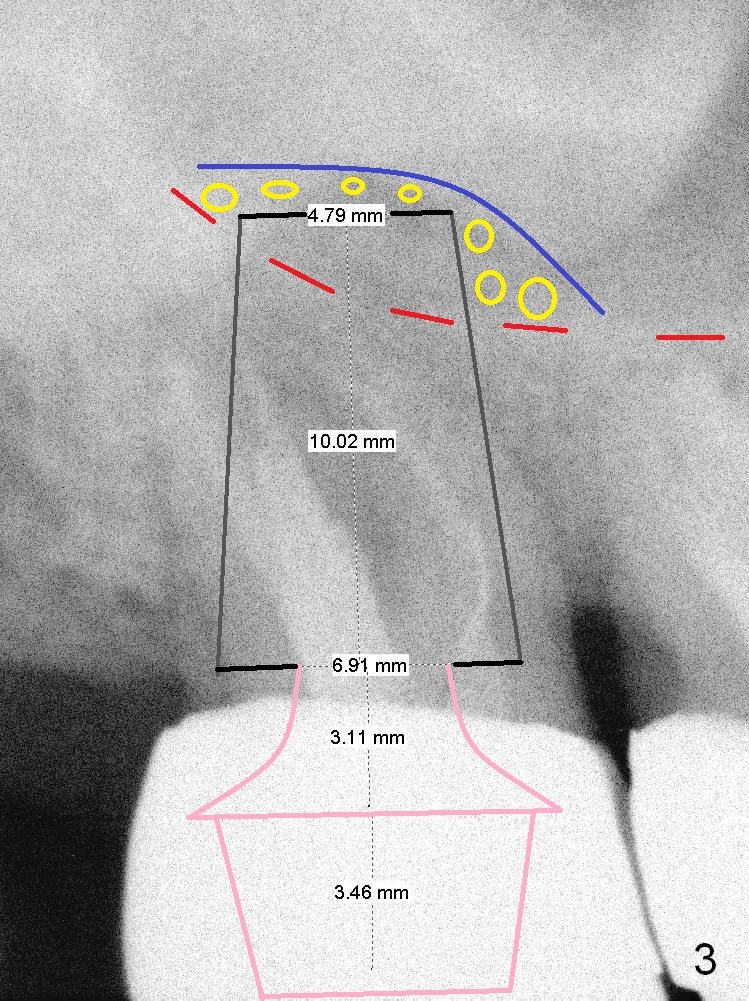

A 59-year-old man is a bruxer, fracturing the teeth #8 and 9. Now the tooth #2 seems to have fractured (Fig.1). Since the apices appear to protrude into the sinus, either 7x14 mm tissue-level (Fig.2) or 6.9x10 mm bone-level (Fig.3) implant will most likely penetrate the sinus floor (red dashed line). To protect the sinus membrane, PRF membrane or plug (blue curved line) is to be placed prior to bone graft (yellow circles) and implant placement. Prepare Magic Expanders and Magic Sinus Lifter. Clindamycin will be used after extraction. Since the roots of the upper 2nd molar usually fuse, prepare large gauzes for hemostasis. Check the buccal and palatal walls for any defect. Start osteotomy away from the defective wall. Place the remaining PRF membrane for wall repair before bone graft. Set stopper 2 mm short of the intended bone-level implant length.